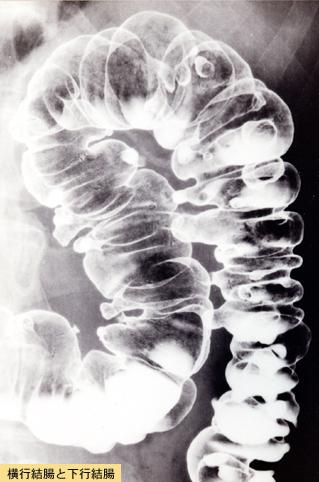

Imágen típica de múltiples divertículos del Colon

Divertículo/Divertículos múltiples

colon/lesión que abarca dos o más regiones del colon

Rayos X

10 - 14